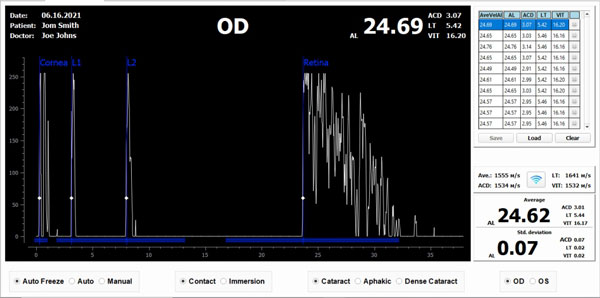

A-Scan

- The A-Scan part of the system performs intraocular distance measurements in seconds using contact or immersion method in either automatic or manual mode.